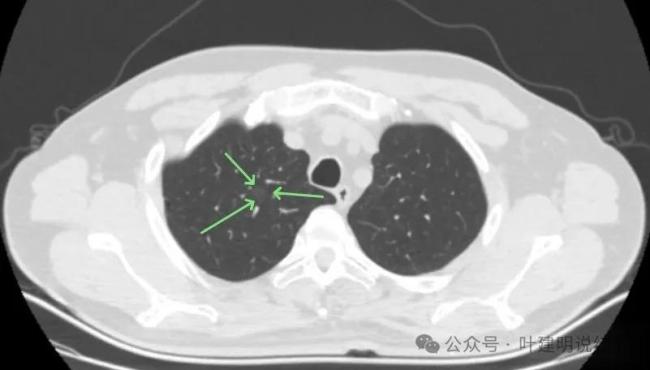

为何选择低剂量CT而非胸片或肿瘤标志物?答案在于“敏感度”。胸片对小于1厘米的肺结节漏诊率高达60%以上,而低剂量CT能清晰捕捉到几毫米的磨玻璃结节。肿瘤标志物则在早期肺癌中多无异常,无法用于筛查。目前,国际和中国指南均唯一推荐低剂量CT作为肺癌筛查工具,其有效性已被美国国家肺癌筛查试验(NLST)证实:连续三年筛查可使肺癌死亡率降低20%。对于像小李这样发现12毫米磨玻璃结节的患者,临床处理有明确路径。中国《肺结节诊治专家共识(2024版)》建议,直径大于10毫米的纯磨玻璃结节,若持续存在,应每6个月复查一次高分辨率薄层CT。若结节增大超过2毫米、出现实性成分,或有毛刺、血管穿行等恶性征象,即应考虑手术。小李的结节在复查中未消退且更明显,符合手术指征,最终通过微创肺段切除,病理确诊为早早期腺癌,术后无需进一步治疗。